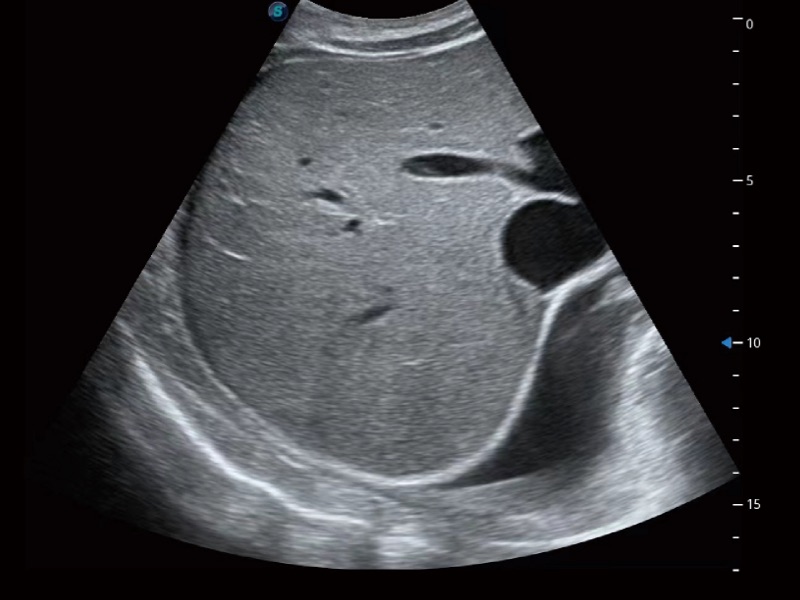

• 腹部应用

临床图